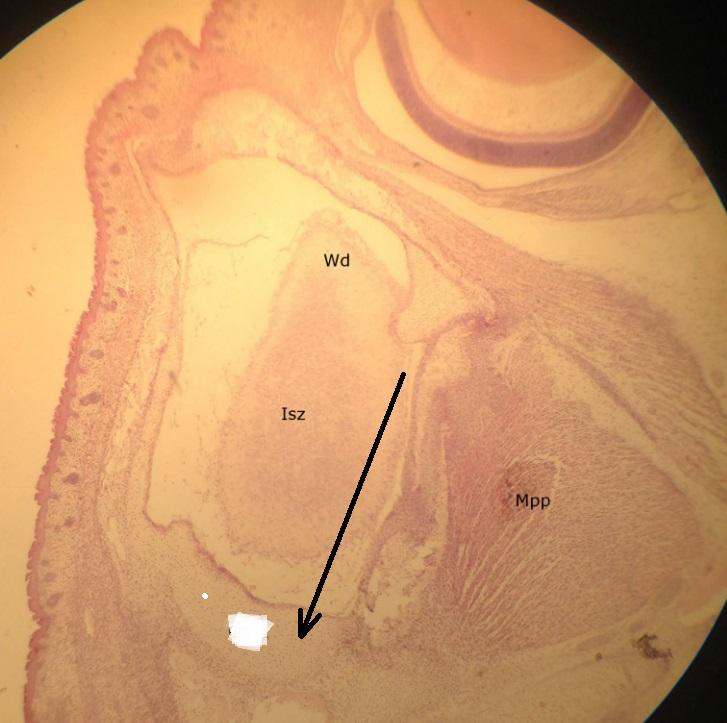

Pytanie 362

kanały półkoliste (preparat rozwojowy z głowy szczura, okolice ucha wewnętrznego)